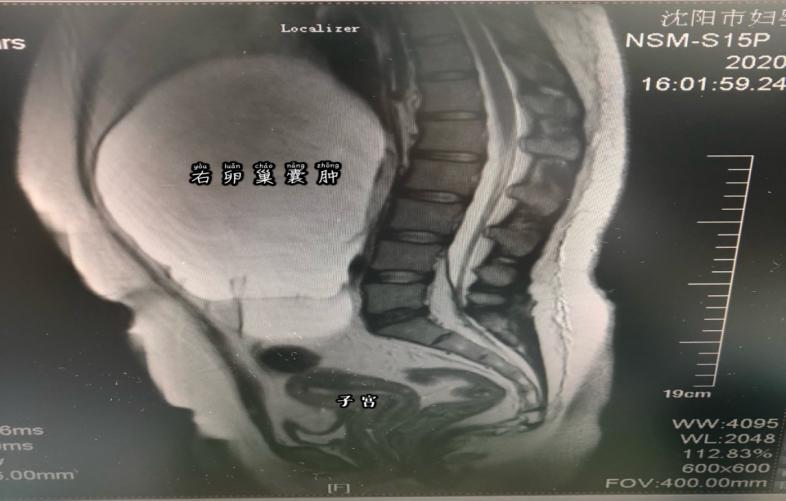

坐在诊室里,被自己肚子里的巨大囊肿吓坏了的孙女士非常忐忑,也十分后悔。其实,在2019年下半年孙女士就发现有点"发福",但因为素来她就比较丰满,以为自己是胖了,也没在意。直到2019年底自己隐约摸到肚子里有个包块,去医院检查才发现是盆腔囊肿。医生当即建议手术治疗,但是因为年底工作繁忙,再加上没有任何症状,也就一拖再拖。结果,因为新冠疫情一直等到2020年5月才来到沈阳市妇婴医院妇科门诊,经过三维彩超及磁共振等检查发现孙女士的囊肿是来源于附件区,最大径线27厘米,已经占据了几乎整个腹腔,手术治疗是唯一选择。

经入院后检查发现,患者腹部包块似足月妊娠大小,而且患者未婚,不仅对生育功能有要求,对美观也更重视。